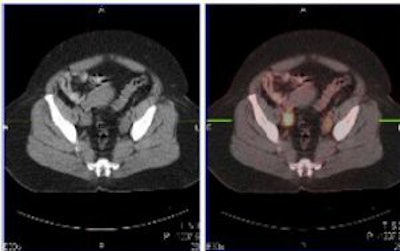

| Above and below, representative images of a 39-year-old patient, currently undergoing treatment, with FIGO stage IB2 squamous cell carcinoma of the cervix. Pretreatment FDG-PET/CT identified an FDG-avid cervical tumor mass plus bilateral iliac and right common iliac metastatic lymphadenopathy. Images courtesy of Dr. Julie Schwarz, Ph.D. |